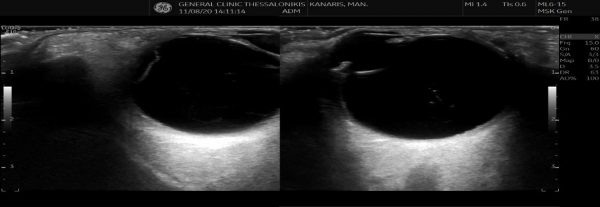

- Έλεγχος των παθήσεων του μαστού σε γυναίκες και άνδρες. Με κλασικό υπέρηχο, έγχρωμο (triplex) και ελαστογραφία μαστού.